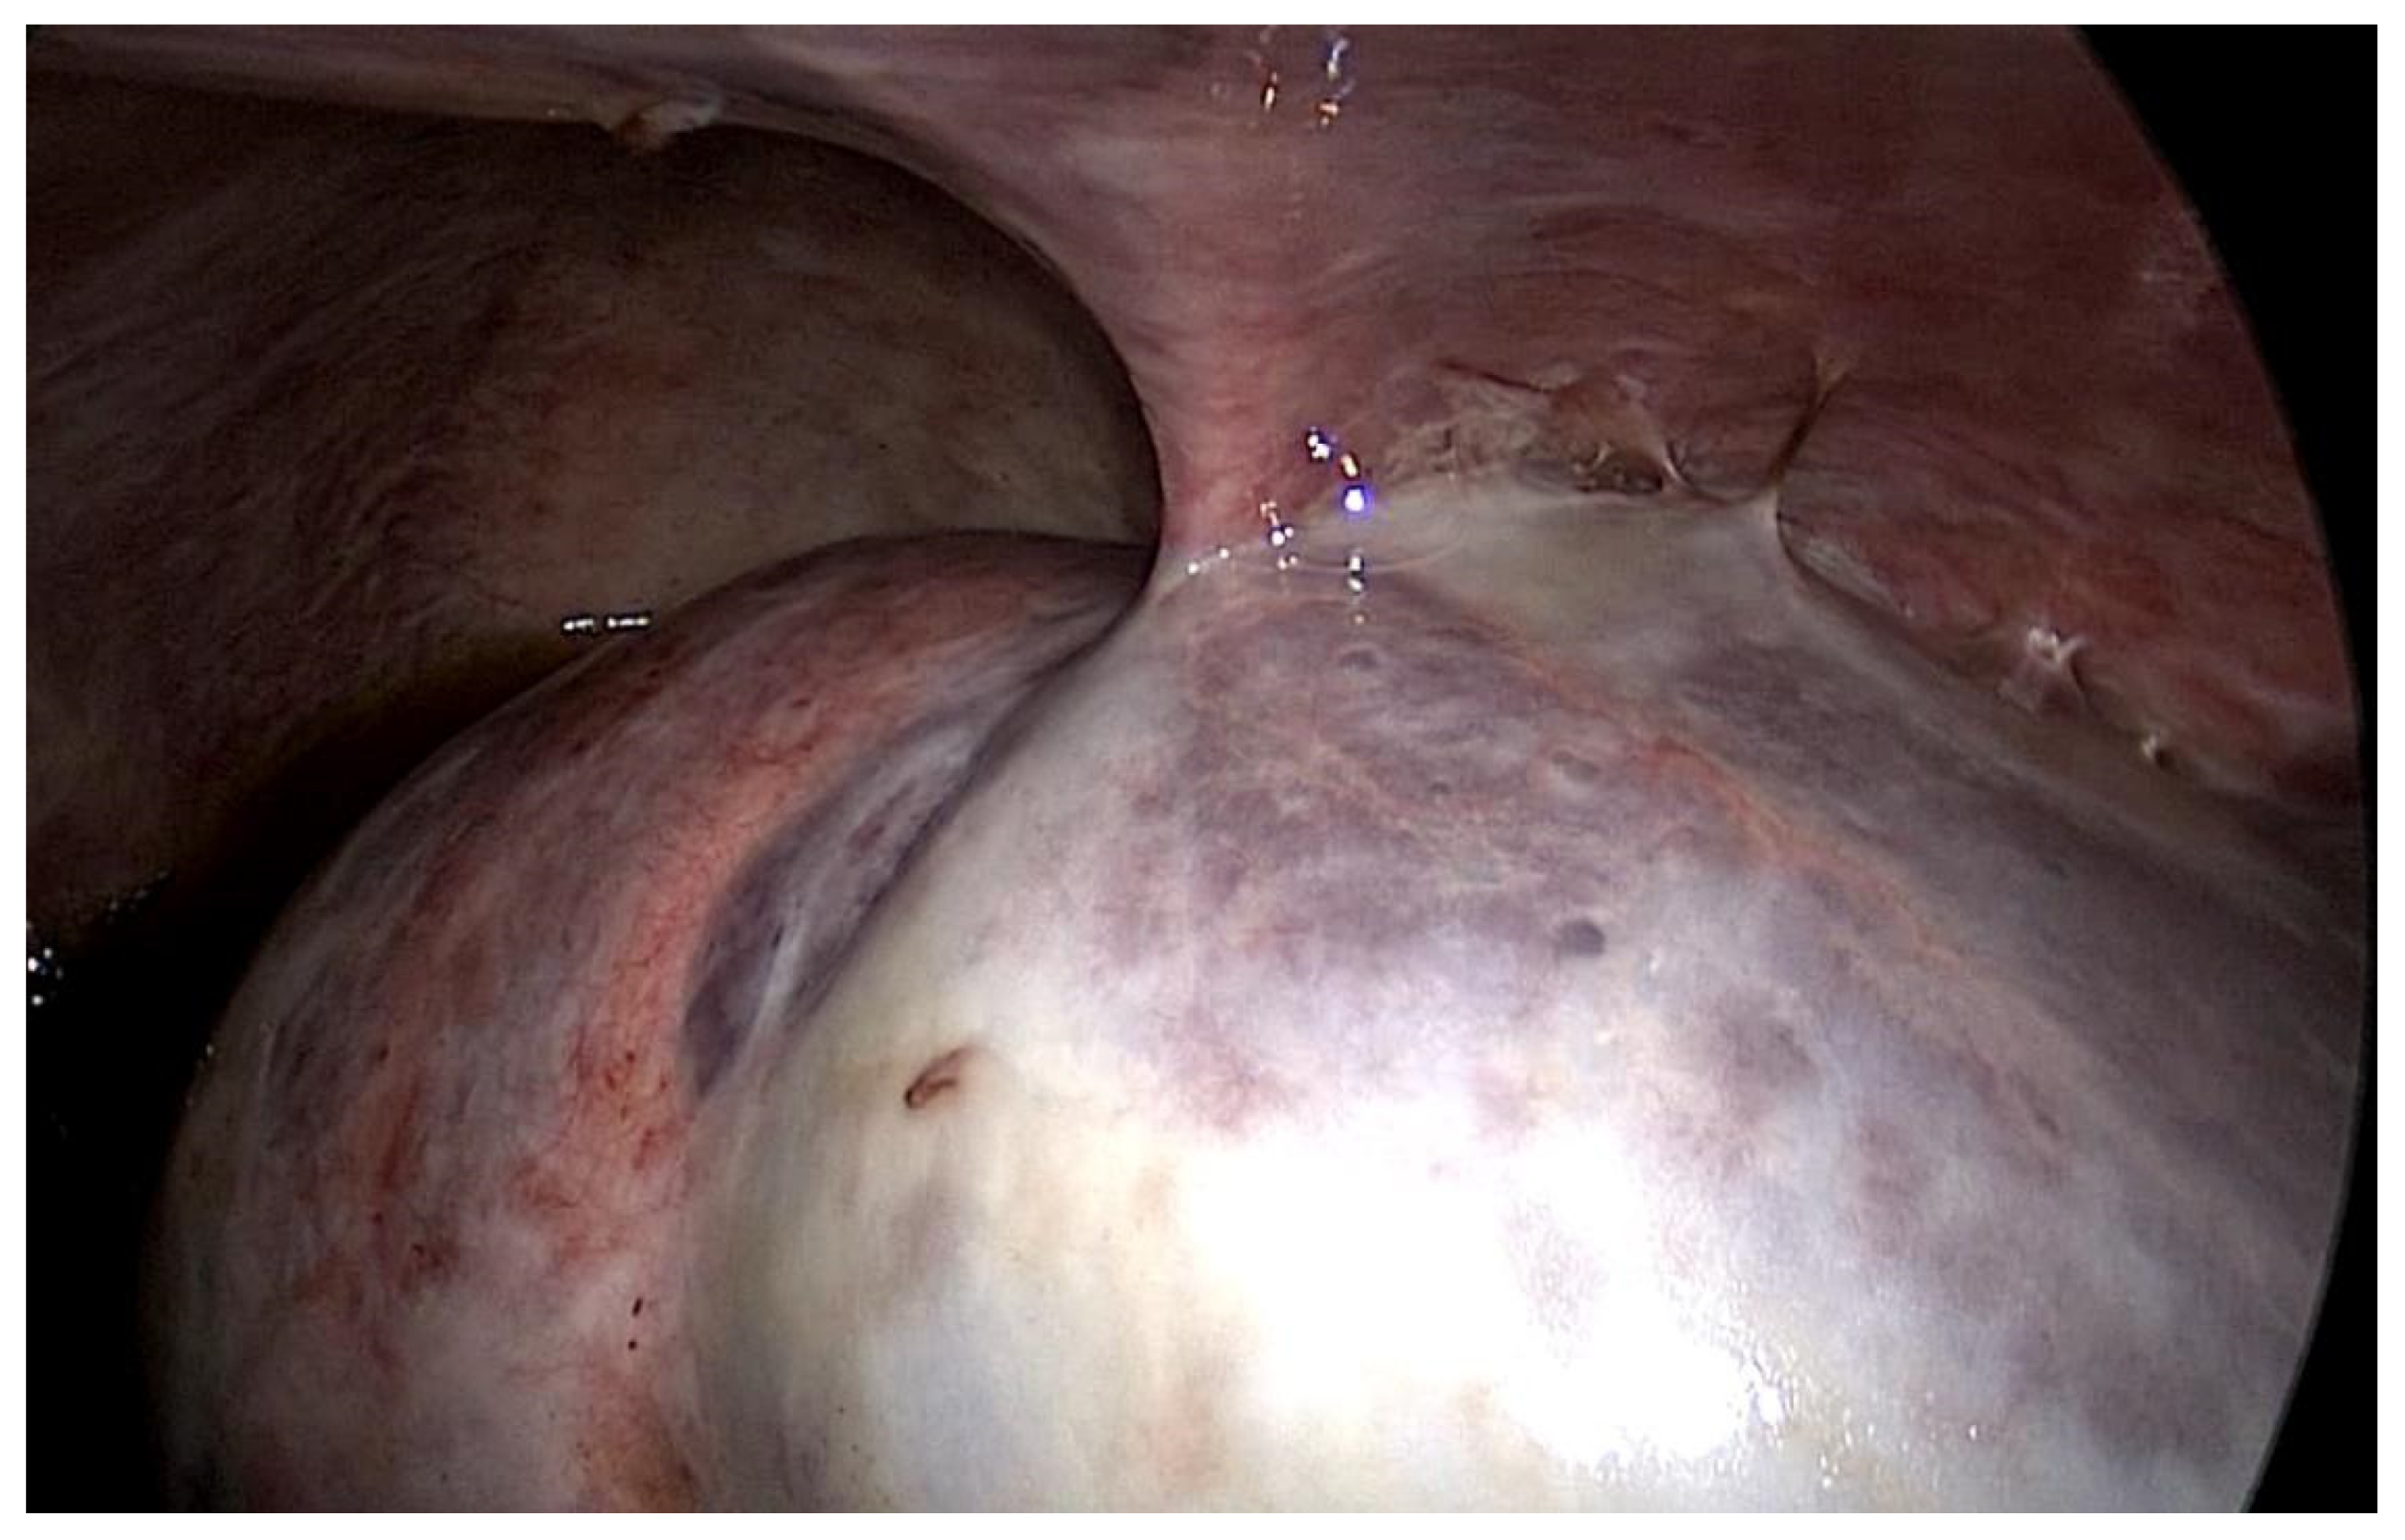

In both of the described cases, optical microscopy revealed lamellar fibrosis, deposits of fibrin on the surface of the peritoneum (Images 3 and 4) and dystrophic calcifications in the peritoneum (Images 5 and 6).

Images 3 and 4. Lamellar fibrosis, condensed fibrin on the surface of the peritoneum, decreased cellularity (haematoxylin and eosin staining, original magnification x100).